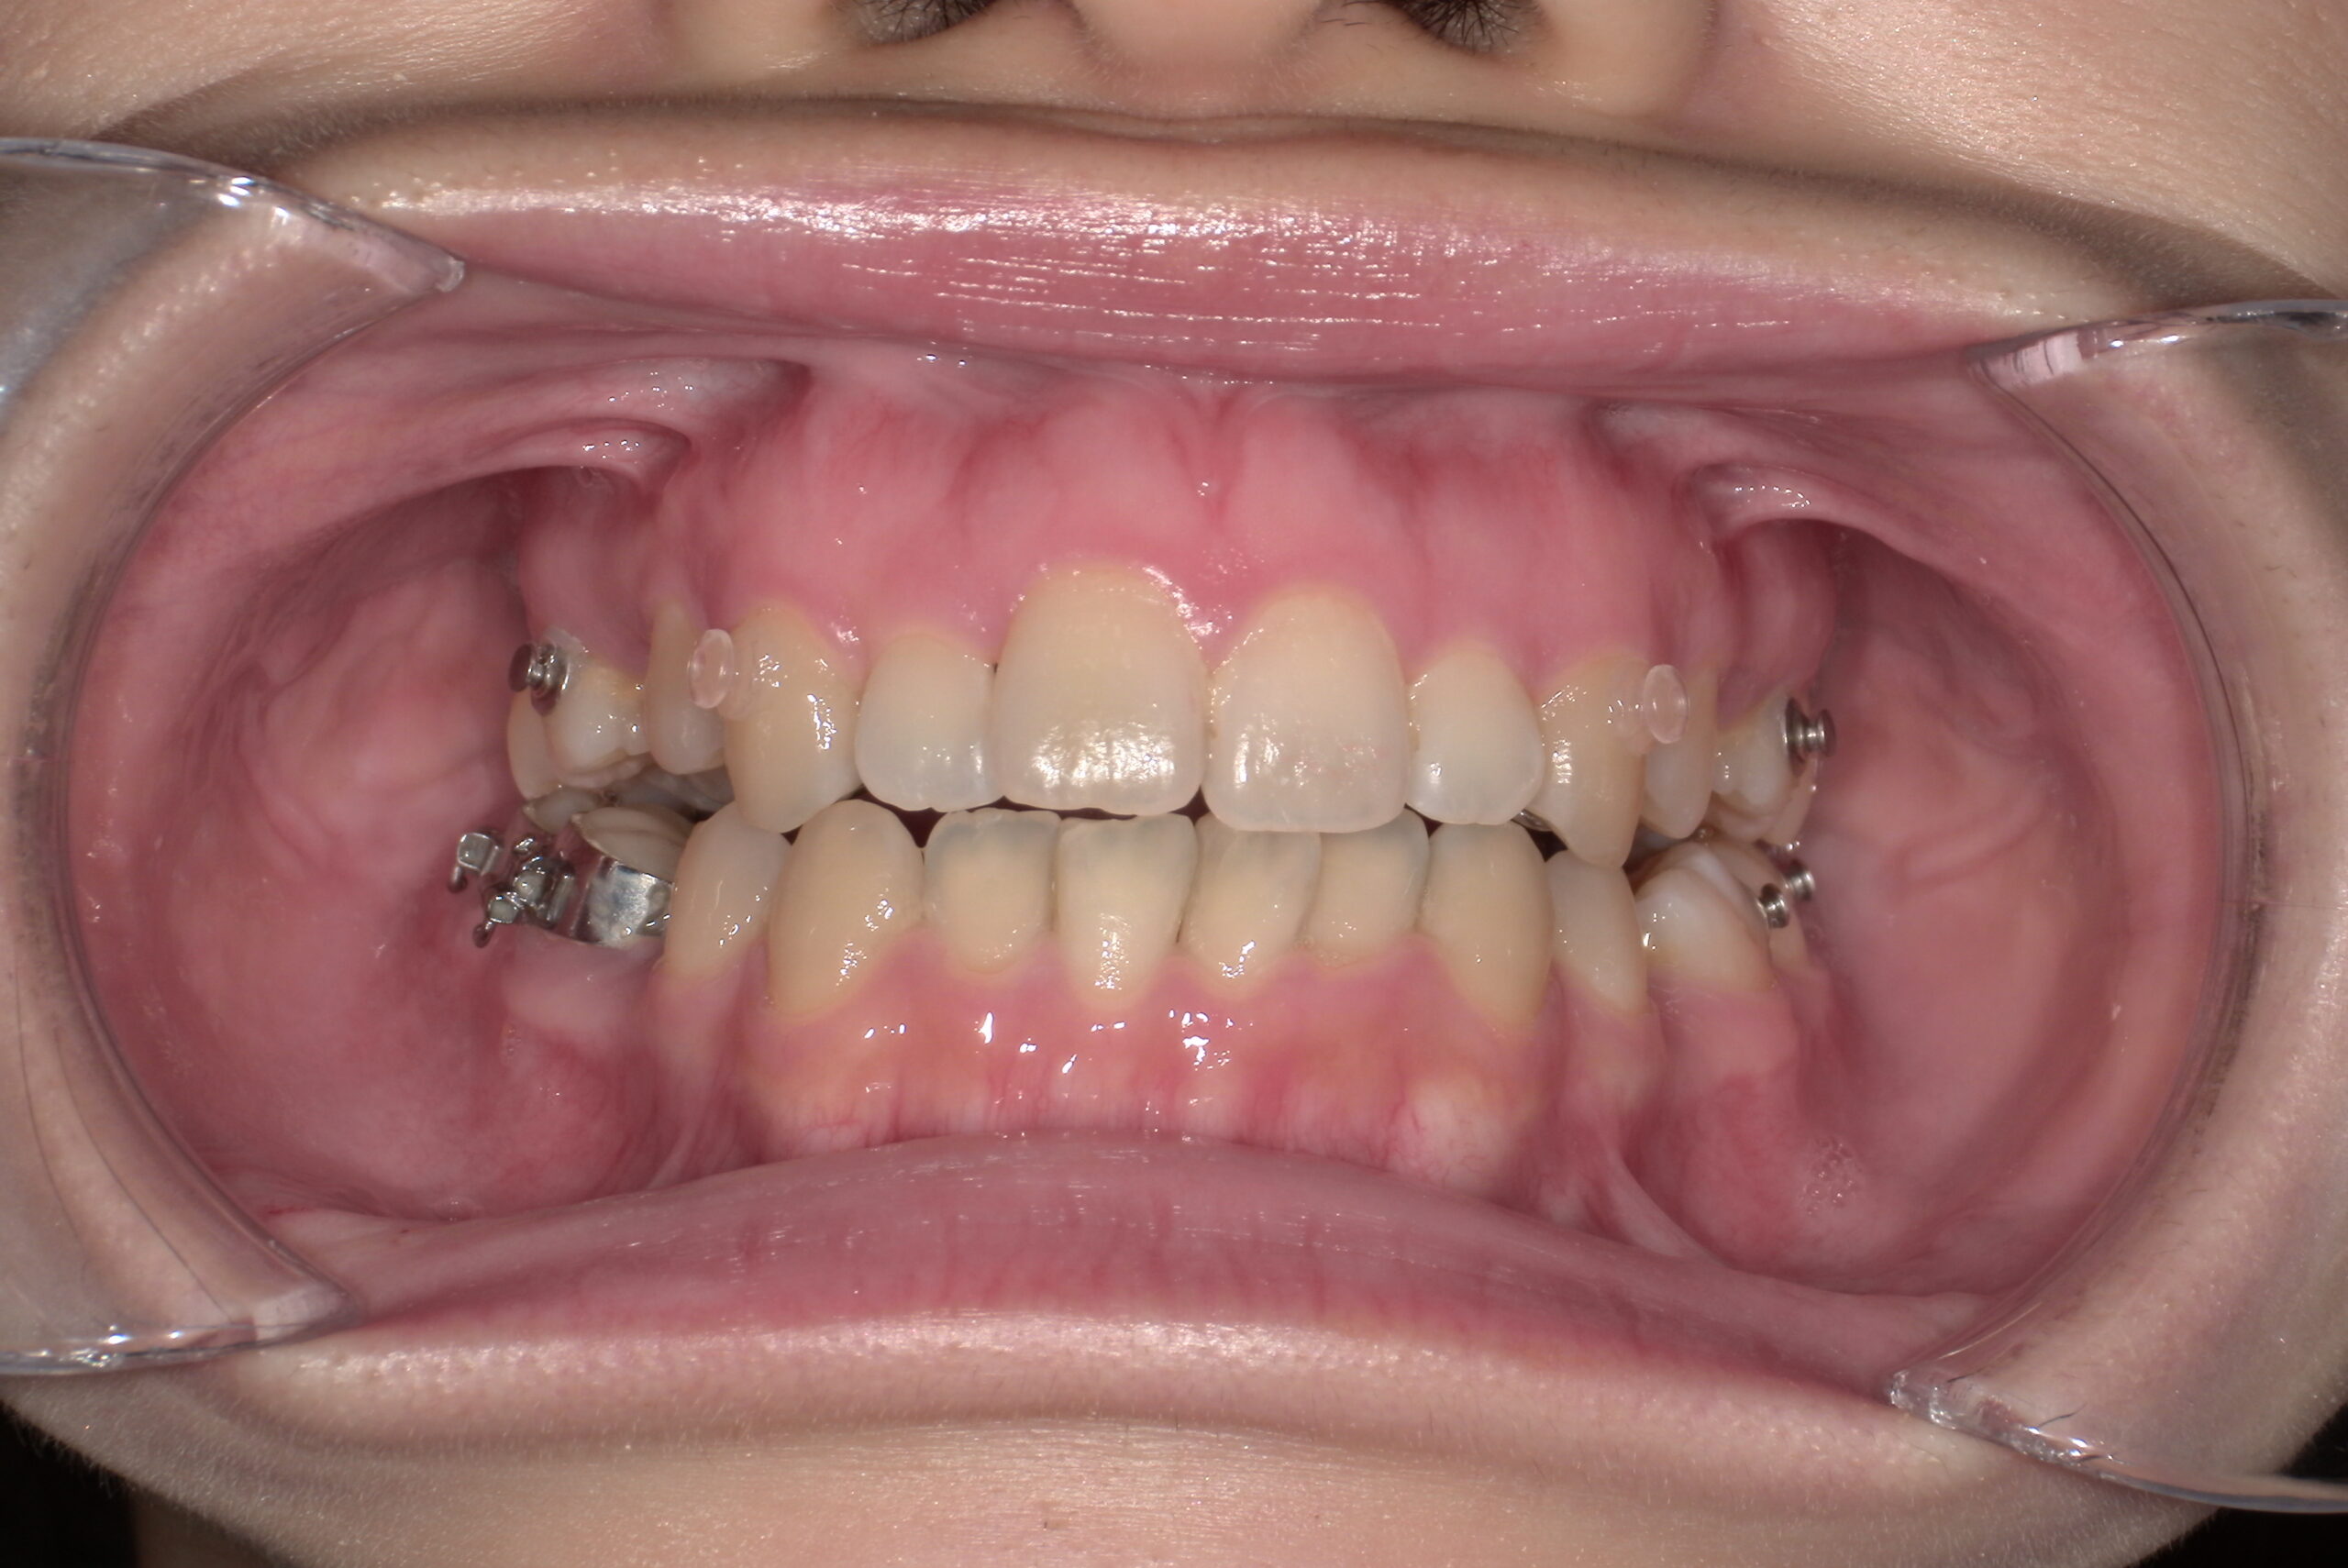

📸治療経過写真

当院で裏側矯正治療しているスタッフの経過写真をご参考にしてください。

上下左右小臼歯を1本ずつ計4本抜歯して現在も治療中です。「歯を抜いた隙間が閉じた量」、「前歯の移動量」、「正面から見た前歯の位置」に注目して見てもらえると、歯の移動の早さが目に見えて分かるかと思います。

初回装着時

正面